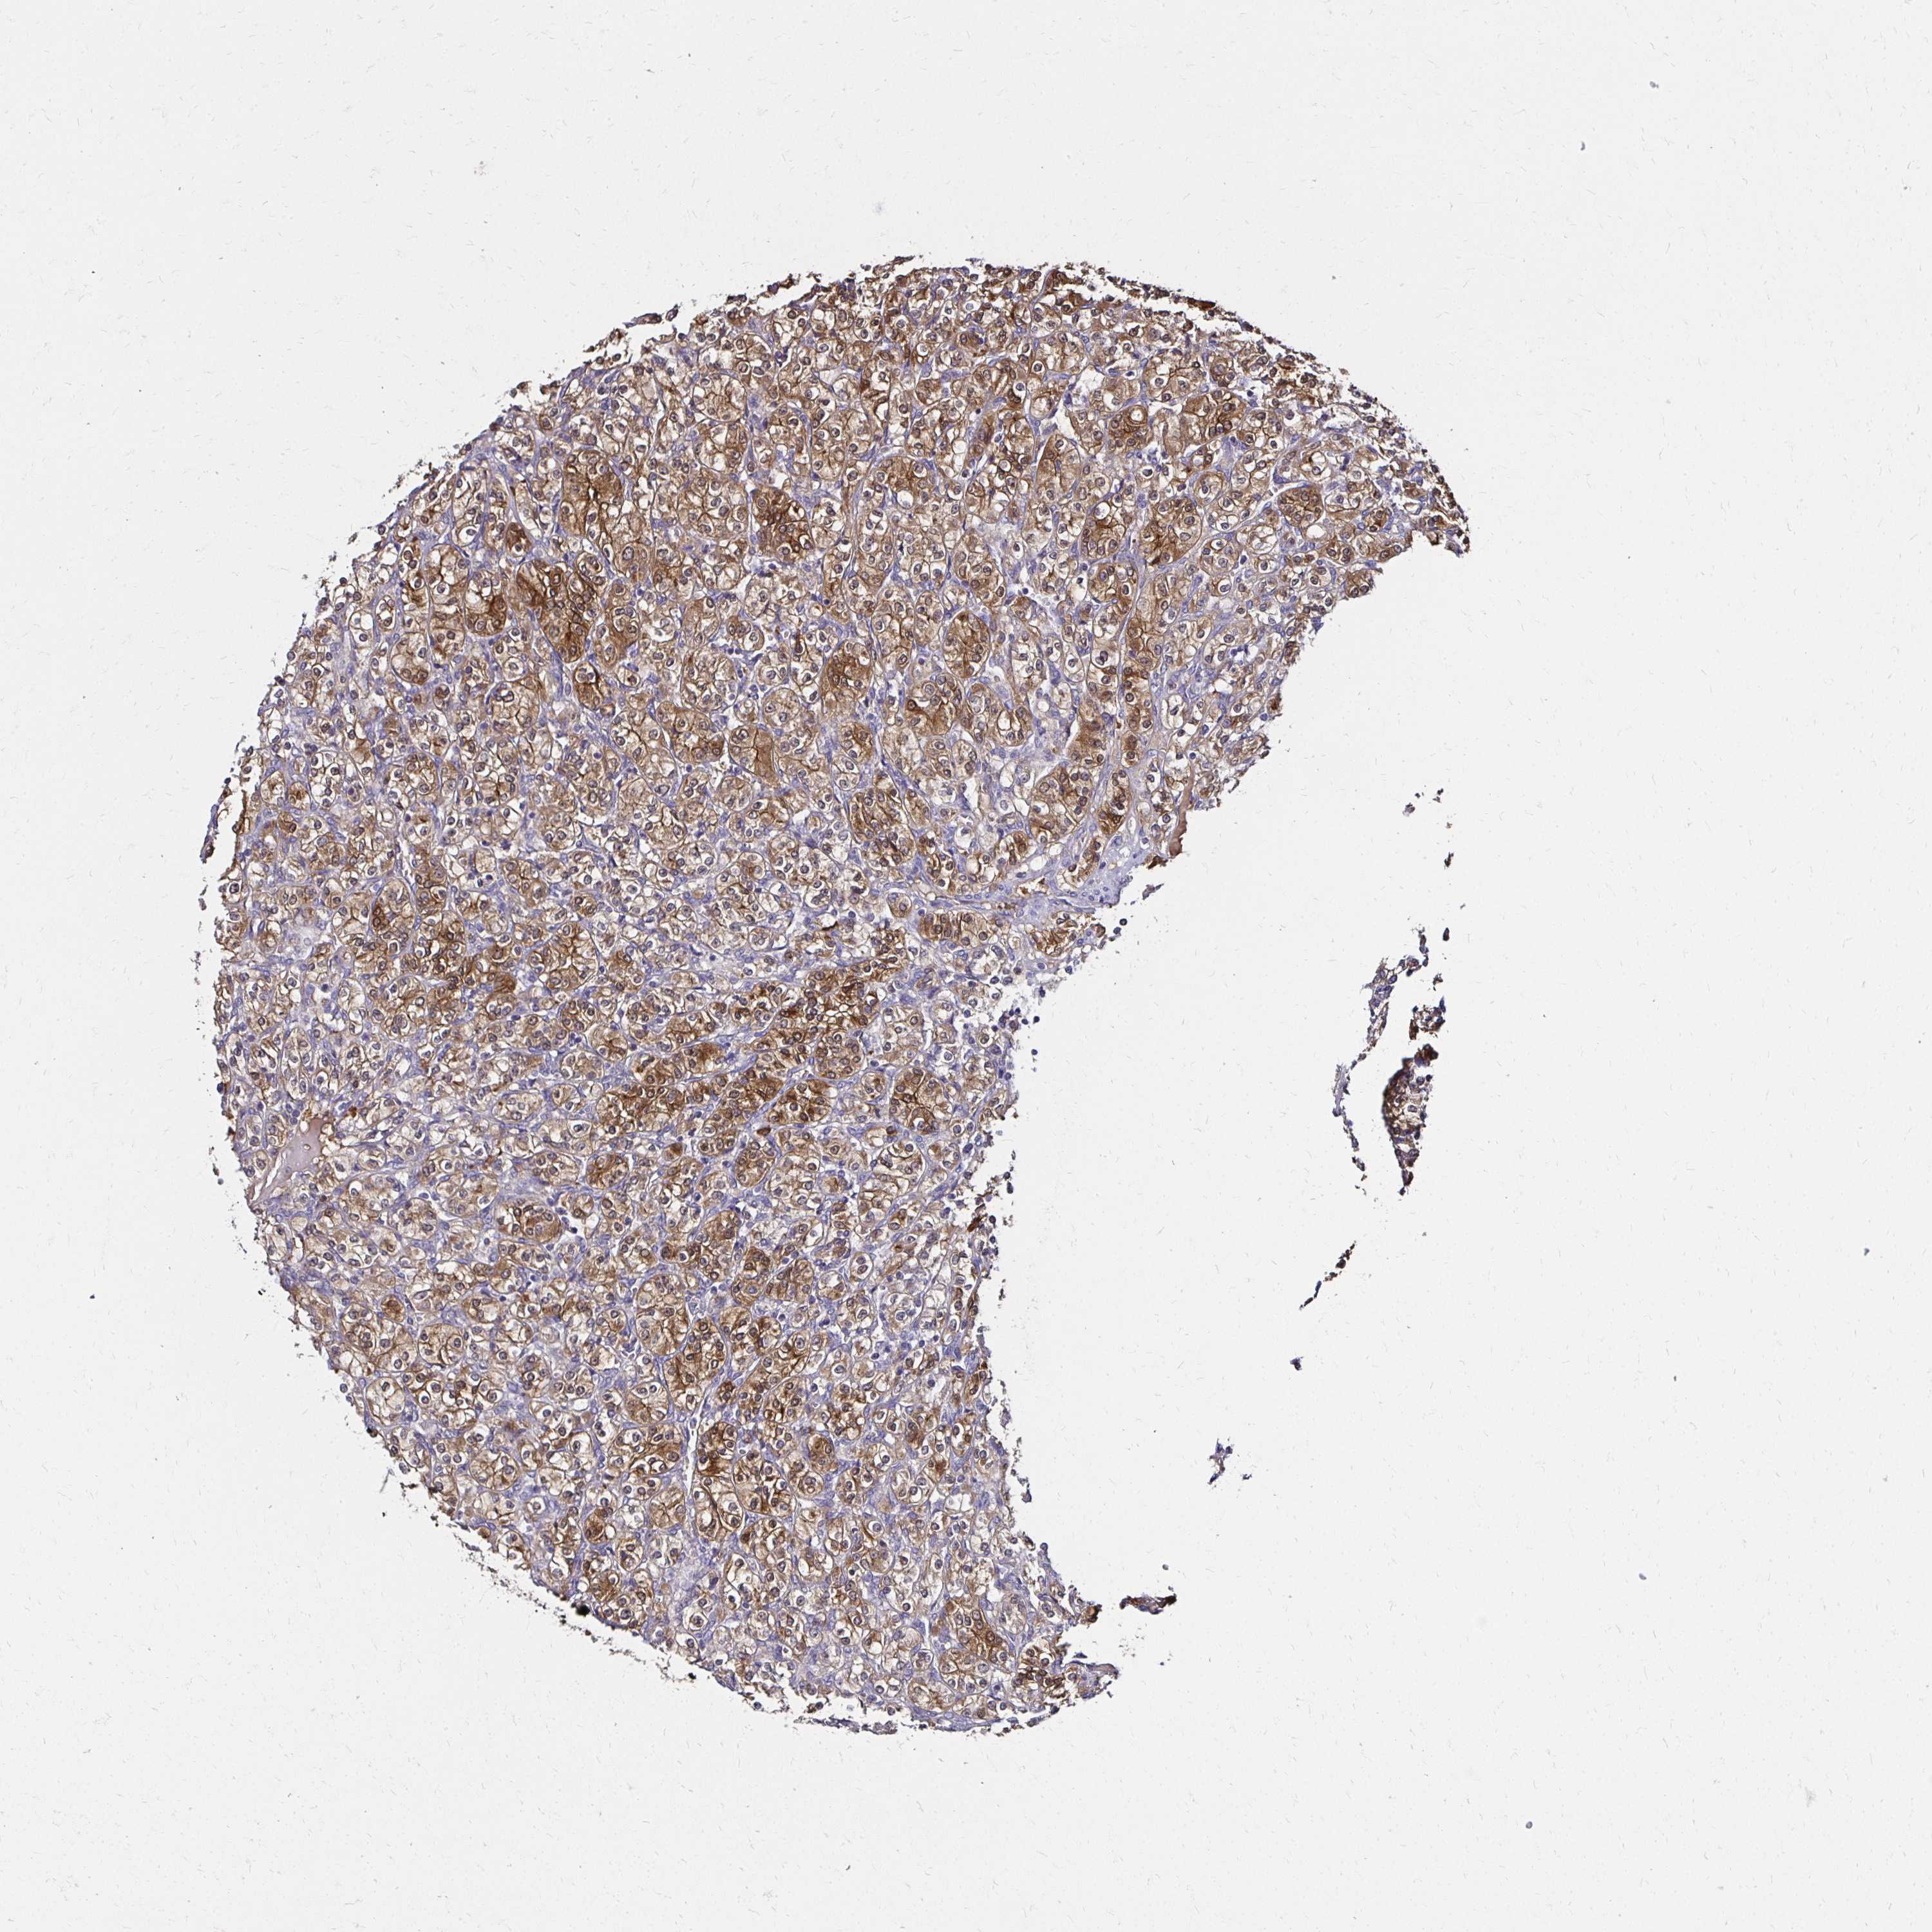

CANCER RENAL CANCER Show tissue menu

KICH TCGA KIRC TCGA KIRC VALIDATION KIRP TCGA PROTEIN RCC CPTAC PROTEIN EXPRESSION